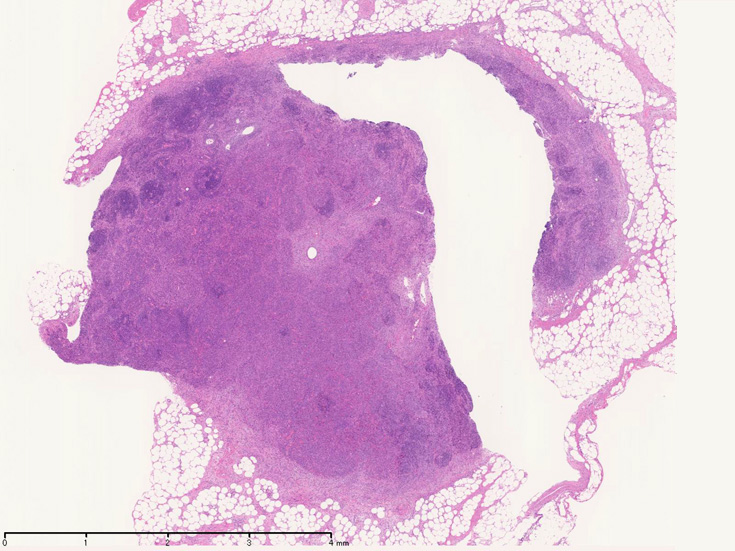

開腹リンパ節生検(腹膜脂肪組織内リンパ節, 割が入っている)

ALKabd01.jpg

Virtual Slide---> 腹膜リンパ節 now available

腹膜脂肪組織内から生検されたリンパ節は基本構造を失っている。低倍率のHE所見では異型細胞が不鮮明な結節構造を形成して増殖している。一次リンパ濾胞を腫瘍細胞が置換しているように見える所見がある。